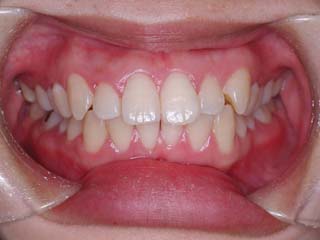

主訴:前歯が出ている

診断名:叢生を伴う上下顎前突

上顎前歯、下顎前歯の前突が見られます。大きな叢生は見られませんが、上下の口唇前突感も伴います。このような不正咬合を上下顎前突と言います。審美的な事もさることながら、歯軸の傾斜の問題から歯にかかるベクトルが良くない事、口唇の筋肉の緊張を強いるような不調和を示す事などから、不正咬合の一つとして考えられています。上顎前突傾向も伴っていますので、積極的に上顎前歯の後退を行う目的で、上顎に固定源となる 目的外使用の オーソアンカー SMAPシステム を装着しました。現在では、歯科矯正用アンカースクリュー(デュアルトップオートスクリュー、ISAアドバンスなど)といった、医療機器認証番号がある製品を用いることが多くなりました。